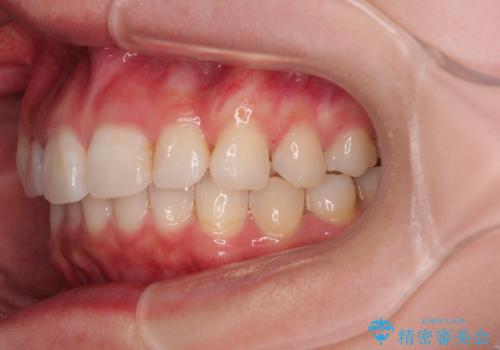

- 前歯のデコボコと突出感を気にして来院された患者様です。

極力目立たない装置を希望とのことで、インビザラインを用いて非抜歯で矯正治療を行うこととしました。

事前に親知らず2本を抜歯し、多少歯列を後方に移動できるように準備をした上で、なるべく歯と歯の間を削ることなくデコボコを解消できるように計画しました。

前歯の捻れを改善するとともに、口元が少しでも引っ込むように治療計画を立て、仕上げることができました。

長時間の装着を徹底し、遠方からの通院にもかかわらずしっかりと通院いただき、予想よりも早く治療を終えることができました。